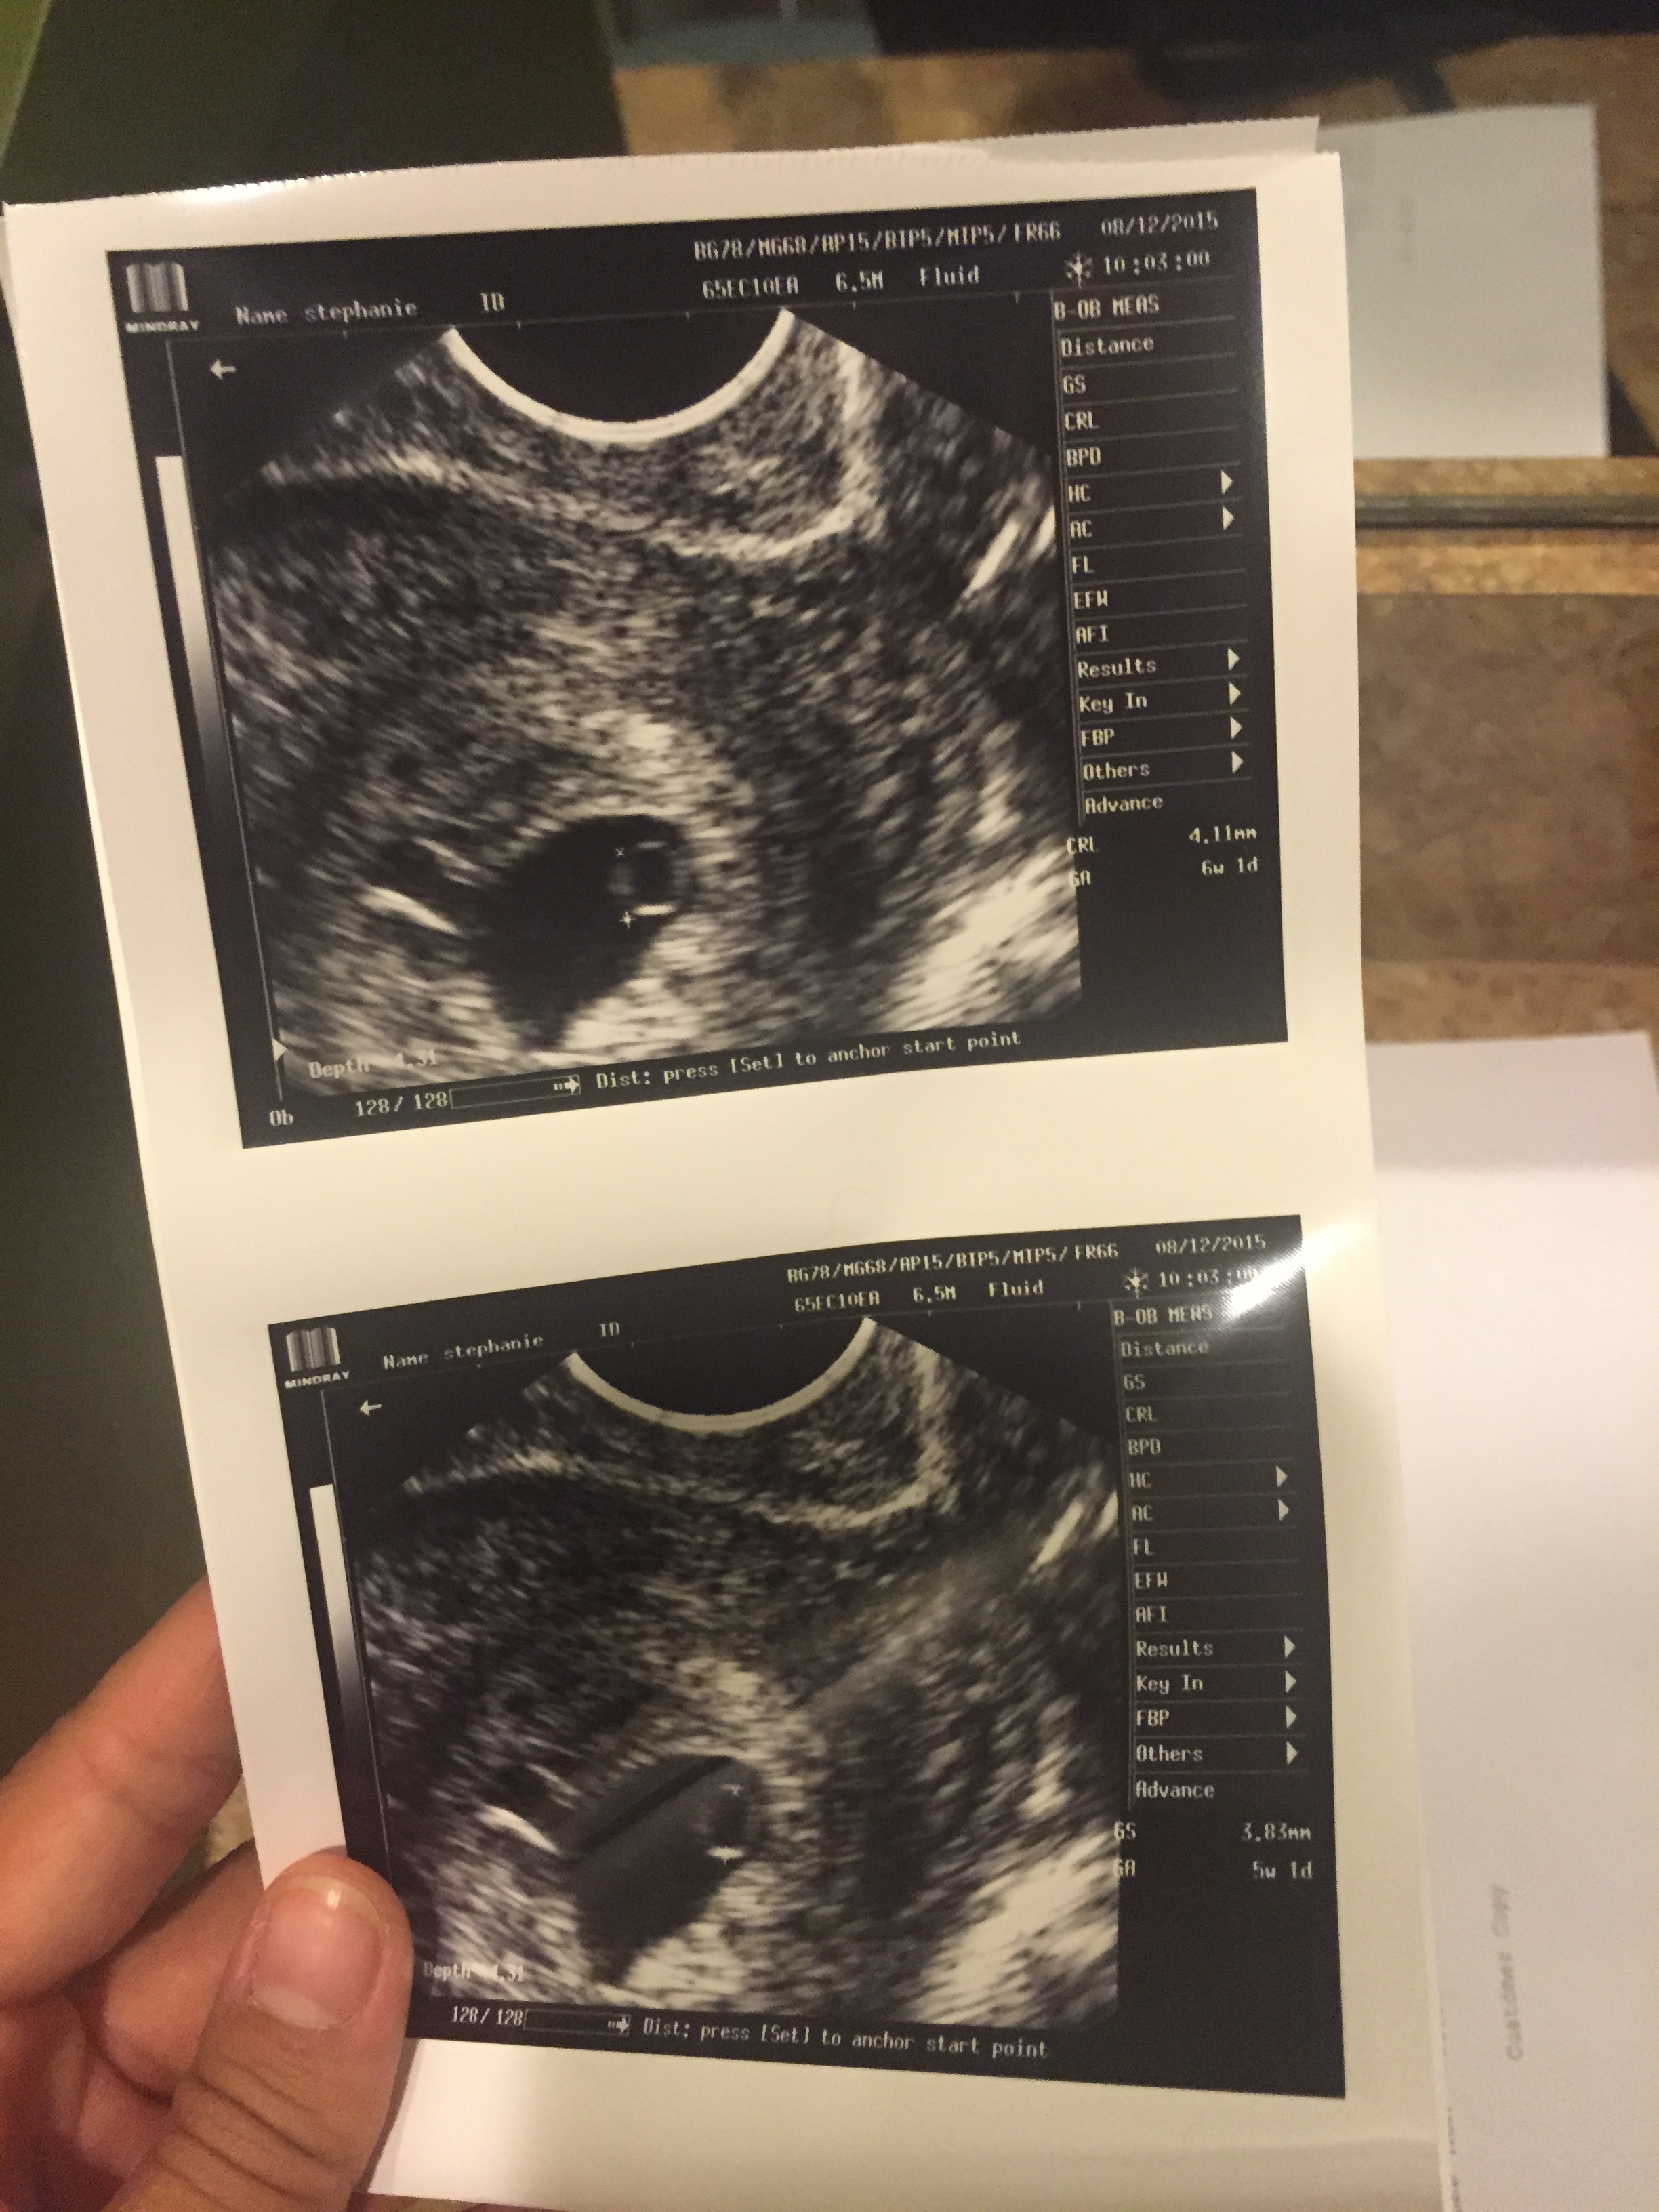

I wanted to wait to tell the rest of the family and friends until our first sonogram. Michael and I were so excited we even asked my doctor bump up our appointment by one week. The excitement to see our baby was too much for us to handle. We got there and couldn’t wait to see our baby’s heartbeat on the monitor. Everything was going fine, until the doctor got really quiet. He sat me up and said he didn’t see what he expected to see and couldn’t find the baby’s heartbeat. I got teary eyed and almost broke down, but I wanted to stay optimistic. Plus I knew that God had already confirmed this pregnancy so I had nothing to worry about. He told me to get blood work done to check my HCG levels. I had test my levels again in two days. Then I got that dreadful call on Saturday. “Steph, I’m so sorry to tell you this, but I ‘m 99% sure you’re having a miscarriage.” I thought NO, he’s wrong this can’t be! I handed the phone to my husband. I felt so numb. I don’t think I’ve ever cried so hard in entire life. I felt empty, completely empty. To know I wouldn’t’ be holding my baby in April Like I had thought completely tore me up. I’m not going to lie, this is going to take a very long time for me to heal. I’m not even close. Even though I instantly blamed God, I know He didn’t want this either. God didn’t want me to loose my baby. He’s the only one that knows why this happened. I prayed for a healthy baby, and maybe this just wasn’t it.

I didn’t want to see my baby pass. That was just too much emotionally for me. I decided to have a D&C. When they called to give me instructions, I broke down. I broke down so hard that my mother in law had to come in the room and just hold me. I let it all out. I cried so hard. I went in the next day to have surgery. I was so sick to my stomach. I couldn’t believe I was going to the hospital to have a D&C. They were going take out my pregnancy. I wanted to run out of there so fast. I thought I would be coming here in 7 months to deliver my baby, not to remove it and go home empty handed. We even double checked with another sonogram and still nothing.